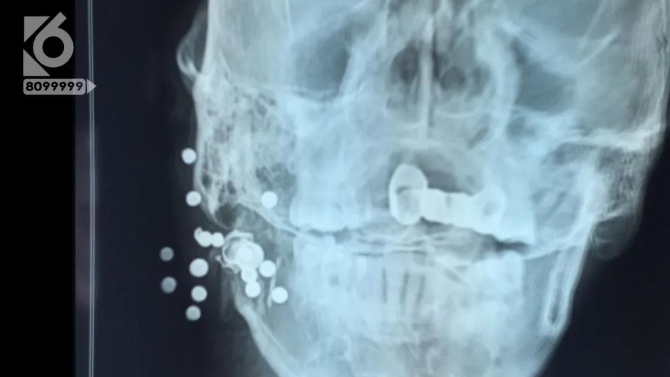

男子臉上中槍轉(zhuǎn)院昆明 醫(yī)生取出11顆鋼珠+彈殼

監(jiān)控顯示,男子被送抵醫(yī)院時,整個頭部都已經(jīng)被包裹得嚴嚴實實,看不出具體受傷的情況。醫(yī)生接診后迅速對男子展開檢查,而這一查,把醫(yī)生都給嚇了一跳。

男子臉部被射15.5顆鋼珠,竟說是“自己走火”?

男子的面部竟然嵌入了有十多顆鋼珠,疑似遭到了槍擊。

昆明骨科醫(yī)院關(guān)節(jié)科副主任 李海波:“家屬和本人自述是二十小時之前,不慎被火器傷打到右側(cè)的下頜部,槍從右側(cè)下頜部進去,子彈穿到耳后這個部位頸動脈這個位置?!?/p>

昆明骨科醫(yī)院關(guān)節(jié)科副主任 李海波:“就可能直接打到動脈,動脈破裂之后沒有搶救的機會,可能當(dāng)場就死亡了,它偏上一點打到下頜骨,下頜骨遮擋了彈珠,避開了重要器官,但是彈夾在受傷后,還是移動了一部分,緊貼著動脈旁邊。”

由于傷者隨時都可能有生命危險,醫(yī)生決定立即實施手術(shù)。而就在手術(shù)前,傷者劉師傅的一句話引起了醫(yī)生的注意。“他是自己走火打到自己的,他自己是這么說的?!?/p>

隨后,劉師傅被送進了手術(shù)室,醫(yī)生一邊做著面部清創(chuàng),一邊取出嵌入面部的鋼珠。男子臉部被射15.5顆鋼珠,竟說是“自己走火”?

經(jīng)過兩個多小時的手術(shù),共取出了十一顆鋼珠和半個損壞的彈殼。

醫(yī)生說:“一共十五顆半,十一顆半都取出來了,還有四顆在氣管里太危險了,不能取了,最危險的彈殼取出來了,彈殼在動脈旁邊呢?!?/p>